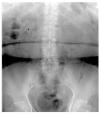

En la Figura 3 se observa como la vena ovárica izquierda ingresa a la vena renal ipsilateral, produciendo ectasia ureteral desde el cruce de las ilíacas, se demuestra que es el sitio donde se cruza el uréter y la vena ovárica, allí se manifiesta la escotadura antes mencionadas, también demostrándose en esta figura la ectasia derecha con gas parenquimatoso hacia el polo superior. En la Figura 4 resalta del lado derecho, justo donde se cruza la vena ovárica con el uréter es donde se produce la ectasia a nivel de la bifurcación de la aorta en ilíacas primitivas, y del lado izquierdo en el cruce ureteral con los vasos ilíacos nuevamente se cruza con la vena ovárica produciendo ectasia.

Figura 4. Lado derecho: cruce de la vena ovárica con uréter, es donde se produce la ectasia a nivel de la bifurcación de la aorta en ilíacas primitivas. Lado izquierdo: en el cruce ureteral con los vasos ilíacos, nuevamente se cruza con la vena ovárica produciendo ectasia retrógrada.